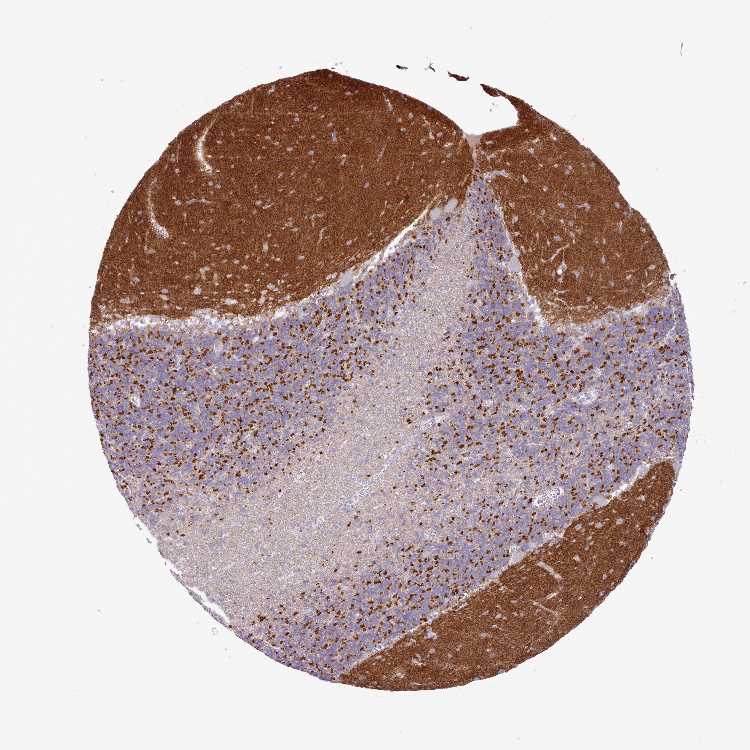

CEREBELLUM - Antibody stainingi

Antibody staining in the annotated cell types in the current human tissue is reported as not detected, low, medium, or high, based on conventional immunohistochemistry profiling in selected tissues. This score is based on the combination of the staining intensity and fraction of stained cells.

Each image is clickable and will lead to virtual microscopy that enables deeper exploration of all samples and also displays staining intensity scores, fraction scores and subcellular localization as well as patient and tissue information for each sample.

Antibody HPA049973

Purkinje cells Not detected

Cells in granular layer Not detected

Cells in molecular layer Not detected